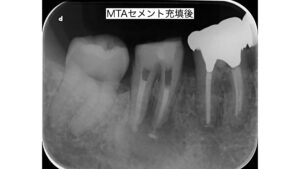

右下奥歯の根の病気に対する精密根管治療

•治療の流れ:ラバーダム防湿 → 根管拡大・洗浄 → 根管充填

•使用器具:マイクロスコープ、NiTiファイル、MTAセメント

•治療回数・期間:3回、約2週間

治療後すぐに歯茎の腫れと痛みは消失しました。

術後のレントゲンやCT画像でも病変(透過蔵)が縮小、改善されていることが確認できました。